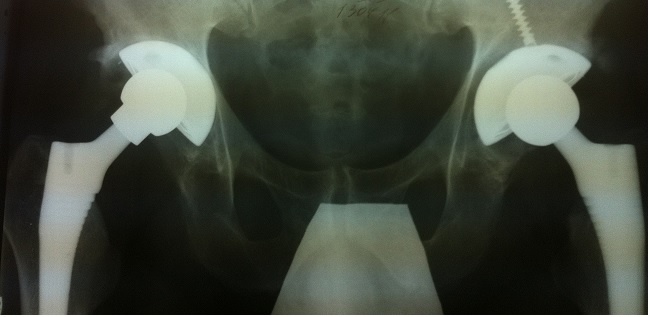

КАК ЖИТЬ ПОСЛЕ ОПЕРАЦИИ ПО ПРОТЕЗИРОВАНИЮ ТАЗОБЕДРЕННОГО СУСТАВА Часть 2 Первые дни после протезирования тазобедренного сустава

Первые дни после протезирования тазобедренного сустава Сразу после операции вы проведете первые сутки в палате реанимации, где за вами будет присматривать врач реаниматолог и медсестра, которые будет своевременно вас обезболивать и восполнять при необходимости потерю крови. После возвращения в палату вам придётся пролежать на кровати еще около суток, затем пациенты встают на костыли и передвигаются самостоятельно на костылях. Впервые дни вы будете бинтовать ноги эластичными бинтами ногами или носить специальные чулки, способствующие кровообращению и препятствующие тромбообразованию. Сроки такой профилактики от 4 до 6 недель после операции, пока не достигнете среднего уровня активности. В этот период температура ноги может быть повышена, может отмечаться отёк, лёгкая болезненность, уменьшить их помогает возвышенное положение ноги, возможно использовать мешочки со льдом. Сколько идет операция по протезированию тазобедренного сустава? Длительность определяется в зависимости от сложности к